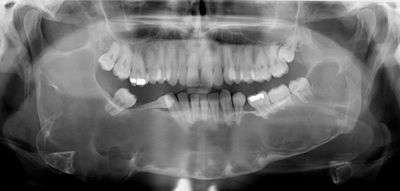

A keratocystic odontogenic tumour (also keratocystic odontogenic tumor, KCOT)[1] is a rare and benign but locally aggressive developmental cystic neoplasm. It most often affects the posterior mandible.

Swelling is the most common presenting complaint; however, KCOTs may be asymptomatic and found incidentally on dental X-rays.[5]

Radiologically

- Odontogenic Myxoma

- Ameloblastoma

- Central Giant Cell Granuloma